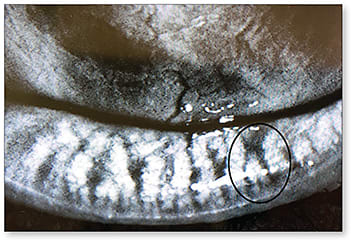

Meibomian Gland Dropout Meibomian gland dropout refers to the complete or partial loss of acinar tissue observed with meibography (Figure 4). Gland dropout is normal with increased age and is not necessarily associated with obstructive MGD. Nonetheless, dropout is a feature of MGD and increases with the severity of progression (Tomlinson et al, 2011). Additionally, loss in meibomian glands is not necessarily correlated with dry eye symptoms unless the tear film is disrupted (Pult and Riede-Pult, 2012).

Figure 4. Meibography of early gland dropout of the inferior lid (circled).